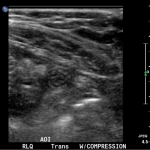

In the long axis video, the appendix appears as an enlarged, non-compressible, blind-ending tubular structure (white arrow) with distinct appendiceal wall layers and lack of peristalsis. In the short axis video, the appendix appears as a target sign (yellow arrow) between the abdominal and psoas muscles. The maximal outer diameter (MOD) measures 11.8mm and the appendix wall measures 0.17mm. There is trace adjacent free fluid and echogenic periappendiceal fat. Transverse axis video and image (red arrow) demonstrate that the appendix is not compressible. These findings are consistent with acute appendicitis.